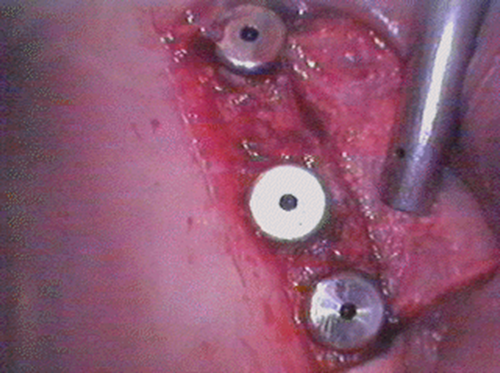

この患者様は、右上の奥歯の歯茎から出血してくるとのことで来院されました。歯周組織検査とレントゲンで診断を行った結果、重度の歯槽膿漏が認められ、保存不可能の為、抜歯になると伝えたところ、入れ歯は絶対に嫌だと言われたので、インプラント治療となりました。CT撮影を行ったところ、上顎洞底までの距離が3ミリ程度しかなかったのですが、骨が固く、フィクスチャーの一次固定が良好だったので、開窓法による上顎洞底挙上術とフィクスチャーの埋入を同時に行いました。約10カ月後に二次手術を行い、上部構造をセットしました。また、右下の臼歯部のブリッジにも大きな二次カリエスが認められ、7番の遠心根が抜歯になり、6番、7番にインプラント治療をしました。